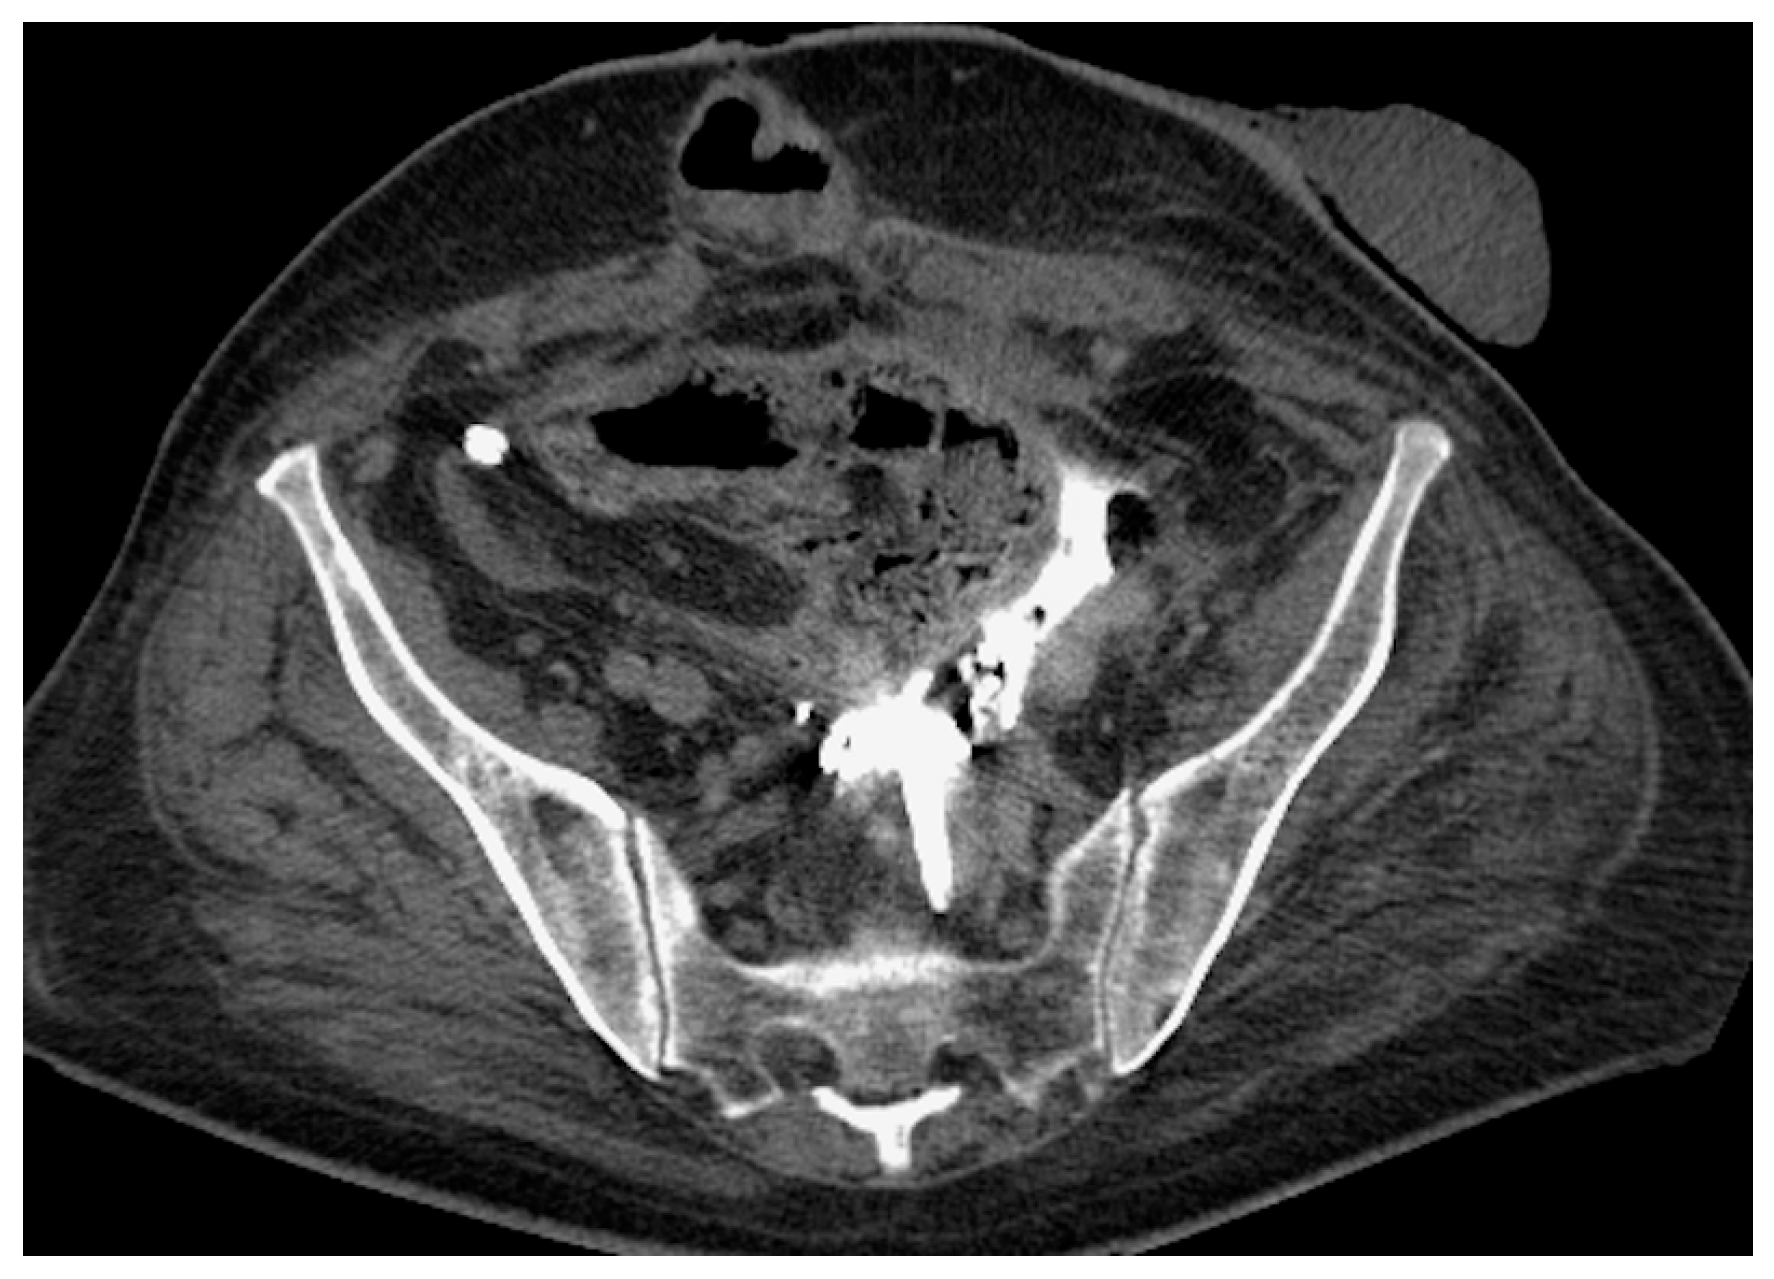

- Malposition: The malposition of a stent is defined as an incorrect position relative to initial placement, while displacement presents a subsequent occurrence in a device that was previously located in the correct position. A stent improperly positioned might assume a sub-pyelic position when the proximal end fails to reach the renal pelvis and a supravesical position when the distal end is detected within the ureter. The origins of this complication predominantly stem from the placement technique, whether it be endoscopy- or fluoroscopy-guided insertion. This underscores the need to verify the accurate positioning of the stent post-placement. Ensuring an adequate length is essential to reduce the occurrence of this complication (Figure 2, Figure 3, Figure 4, Figure 5 and Figure 6) [21,22].

- Stent Knotting: It is a rare complication. Most of these knots involve the proximal end of the stent near the coil, but every portion can be affected [27,28]. Previous reports have attributed knot formation to the excessive length of the stent, stent shape (double-J or multicoil), and flexibility or anatomical abnormalities, such as cystocele and ileal conduits. An abdominal X-ray and, especially, a CT scan are more sensitive than other imaging modalities in identifying a ruptured or knotted stent as well as its migration (Figure 7) [29,30].